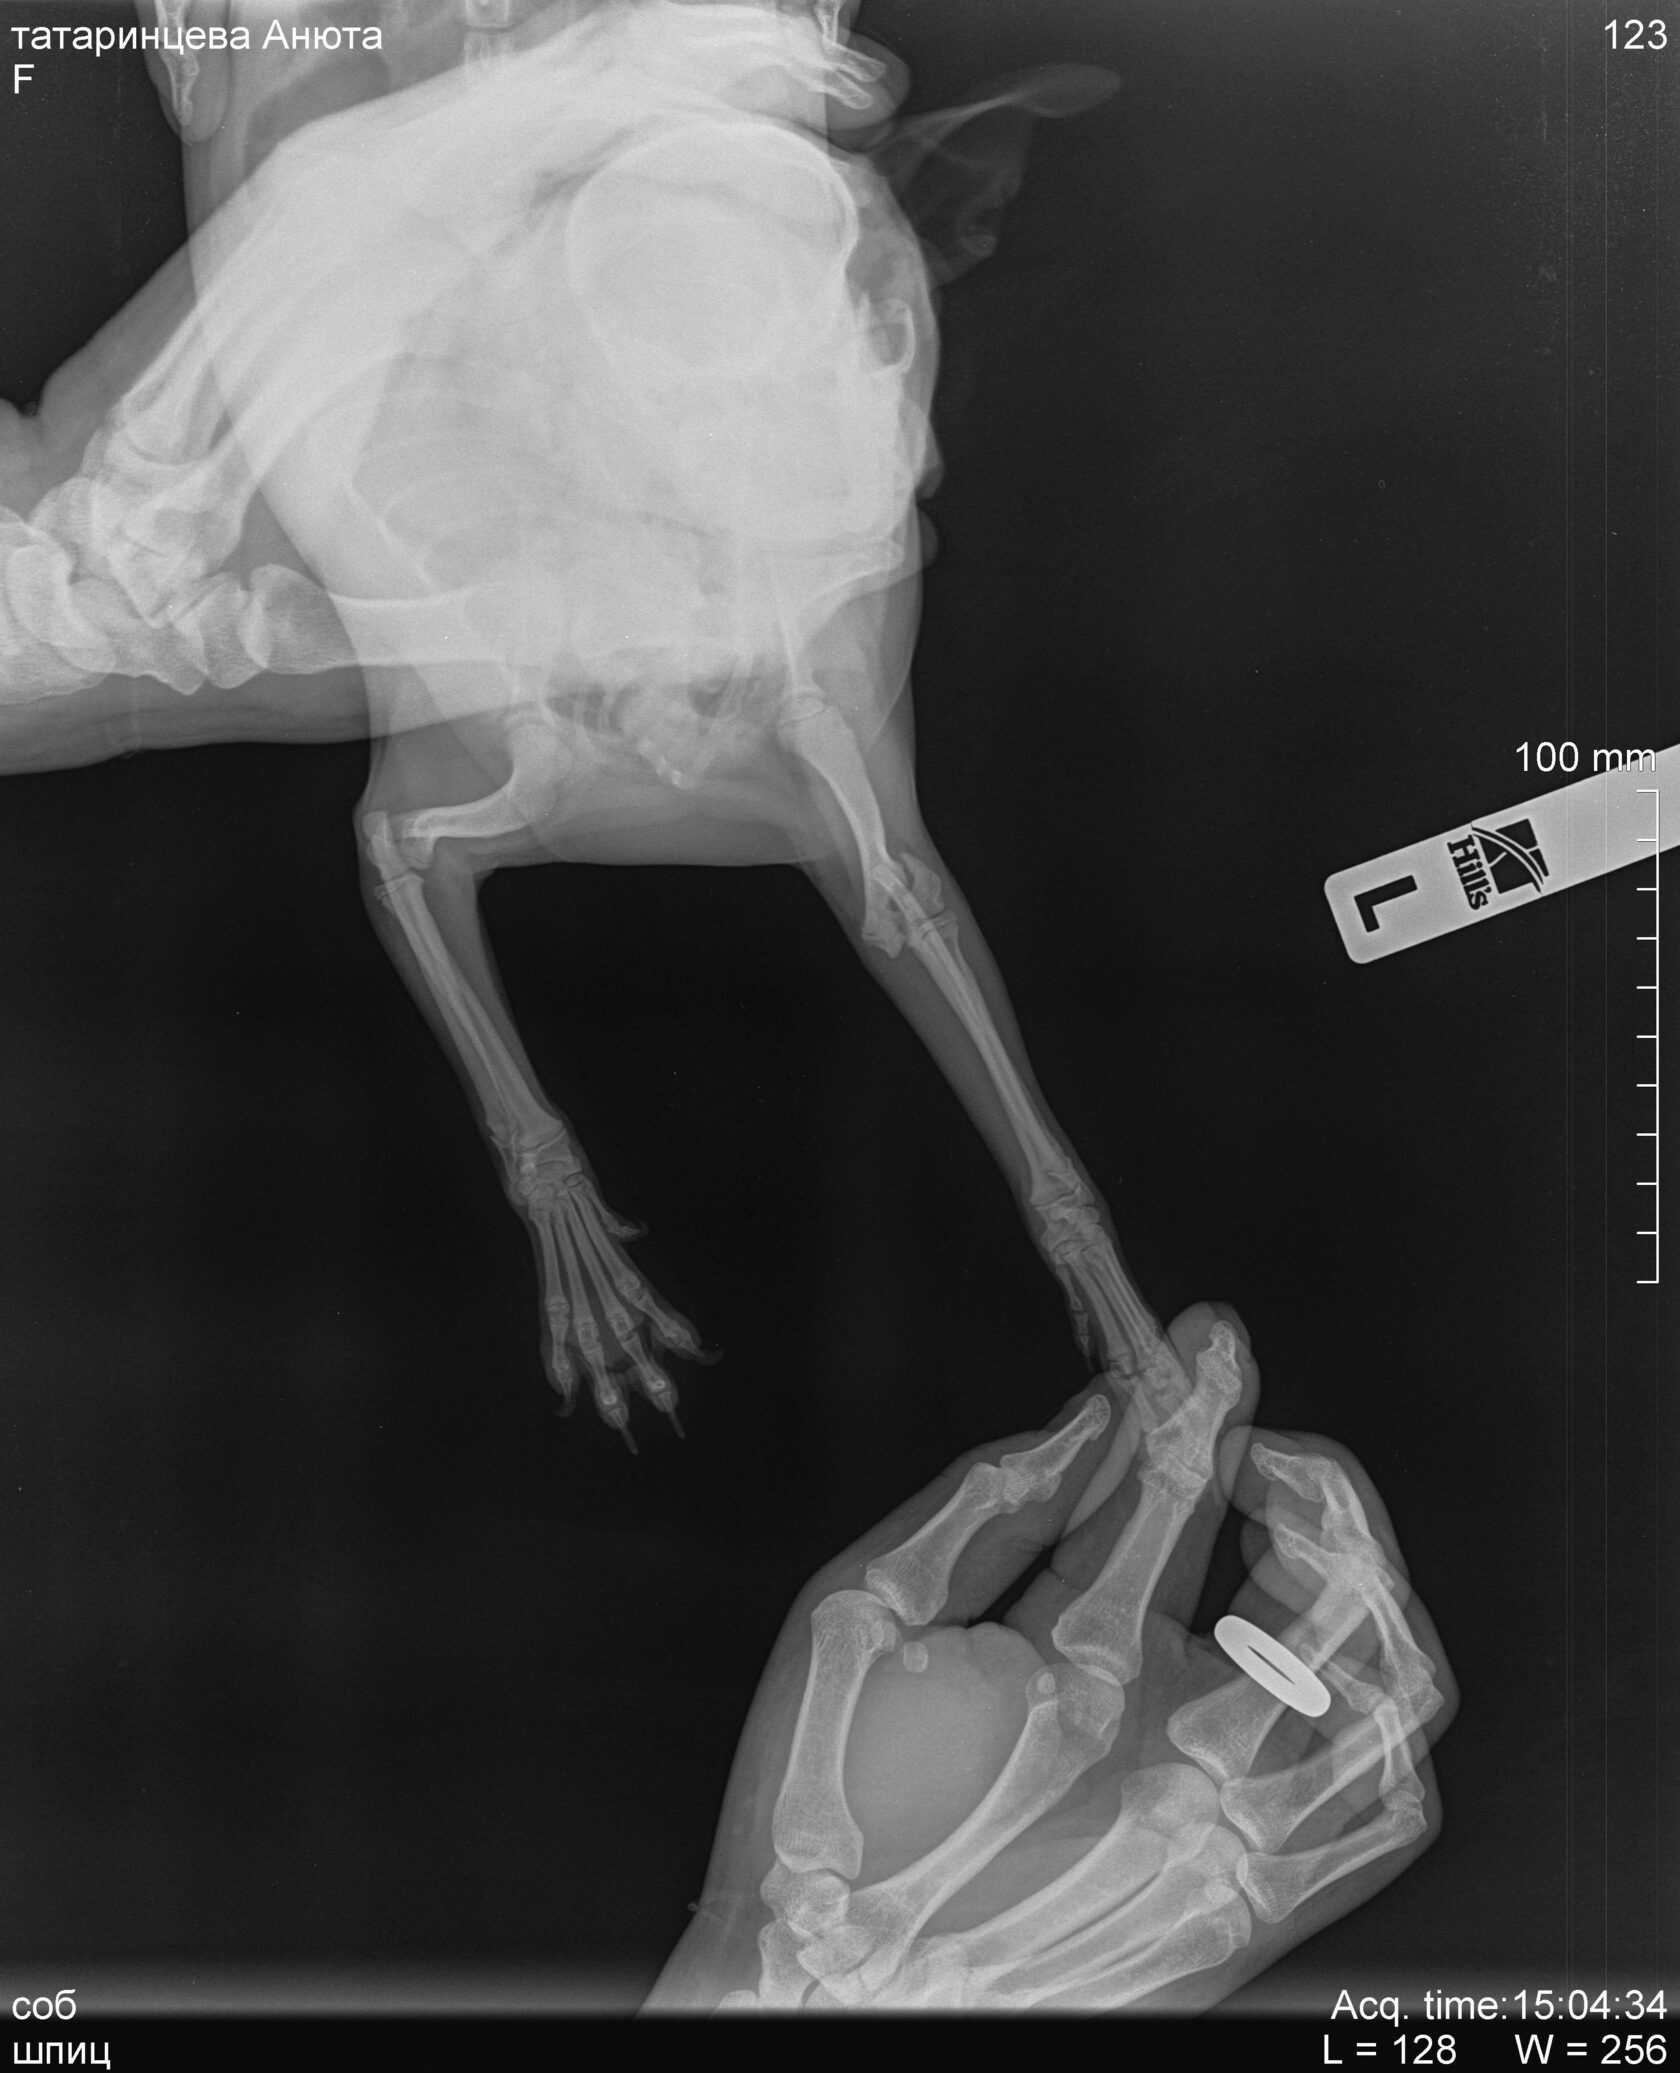

Рентгенограмма в дорсовентральной проекции левой грудной конечности, перелом латерального мыщелка плечевой кости вследствие прыжка со стула.